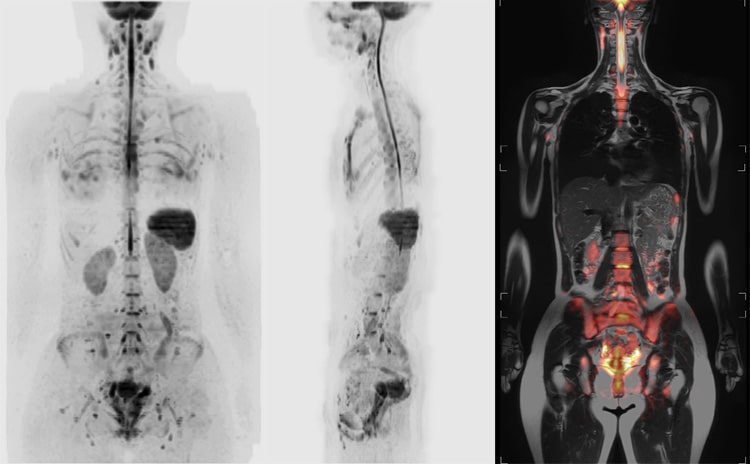

みなさんは「DWIBS(ドゥイブス)」という検査を聞いたことがありますか?

DWIBSは、MRIを使って首から骨盤を撮影し、がんや炎症などの異常を見つける検査です。

DWIBSでは、体の中の水分の動きを画像として見ることができます。

がんがある部分では細胞が密集しているため、水の動きが制限され、その場所が明るく光って映し出されます。